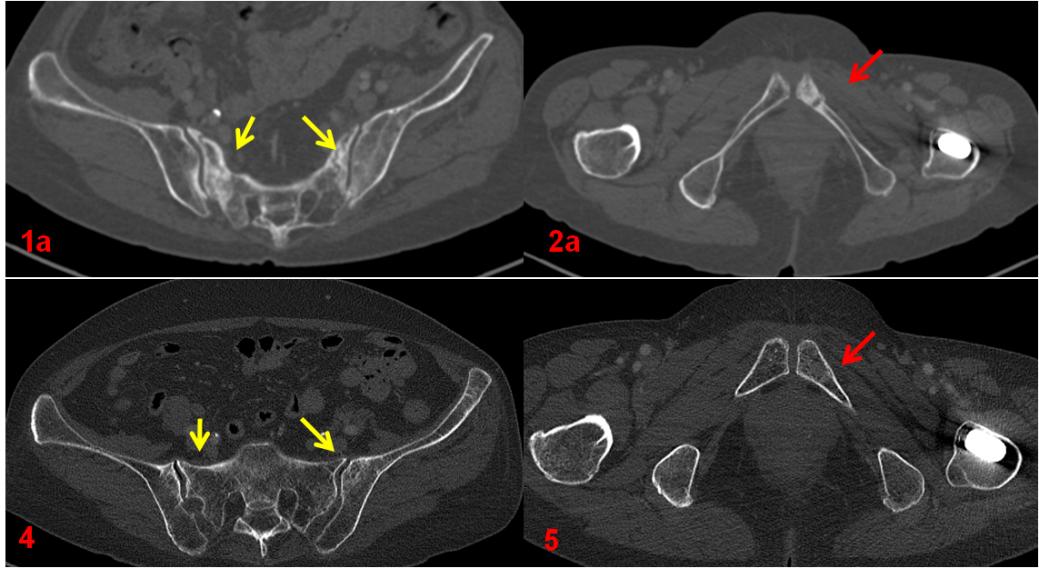

復查CT(圖4、5)對比前片(圖1a、2a)。前片所示骶骨密度不均勻增高(1a,黃箭),本次明顯恢復(4,黃箭),左側(cè)恥骨骨質(zhì)斷裂(2a,紅箭),本次基本消失(5,紅箭)。